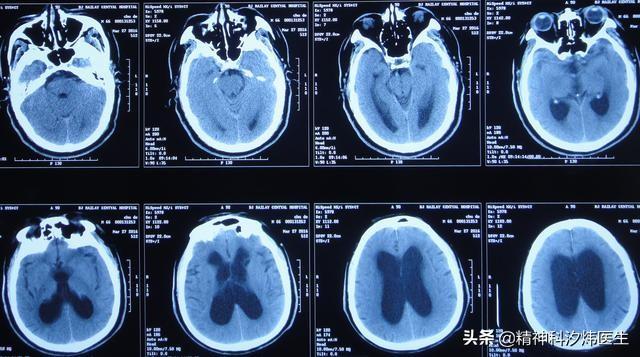

近年来通过分裂症的大量研究,发现患病个体,经脑核磁检查大多有以下变化:脑室扩大、脑皮层、额部和小脑结构变小,除此皮质厚度变小、脑沟回增宽、脑重量减轻等。但是,这些也仅仅是在部分死亡患者机体上查找到的共性,倘若作为发病原因,我们仍无法直接的进行筛查或研究。